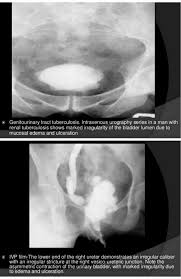

Thimble Bladder Sign Tuberculosis Involvement Of The Bladder May Cause Calcification In The Wall Which May Become Thick And Reduce Th Radiology Bladder Signs

Thimble Bladder Sign Tuberculosis Involvement Of The Bladder May Cause Calcification In The Wall Which May Become Thick And Reduce Th Radiology Bladder Signs from www.pinterest.com